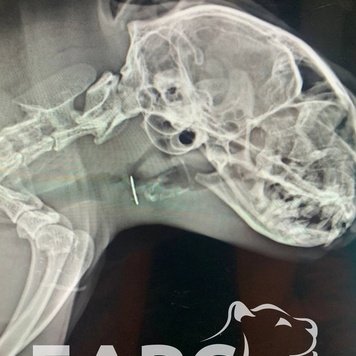

Соня - домашняя кошка, и хозяева очень внимательны к ней. Но за кошками не всегда удается уследить, тем более если они очень любят играть с нитками (вспоминаем "новогодних" кошек с дождиком внутри). Обнаружить иголку удалось при помощи рентгенографии. Положение ИТ было таково, что извлечь его эндоскопическим способом было невозможно. Анна Владимировна Дроздова, врач-эндоскопист, хирург, главный ветеринарный врач Клиники БАРС, приняла решение удалить иглу, сделав небольшой надрез на шее.